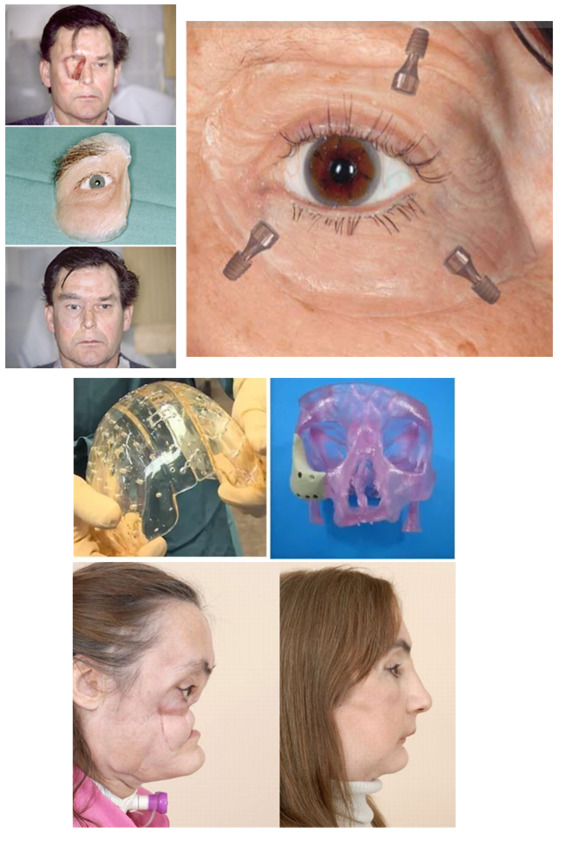

Внеротовые имплантаты головы

Внеротовые имплантат головы

Этот вид имплантатов применяется для косметического восстановление утраченных вследствие травмы или в результате операции, связанной с удалением части тканей головы.